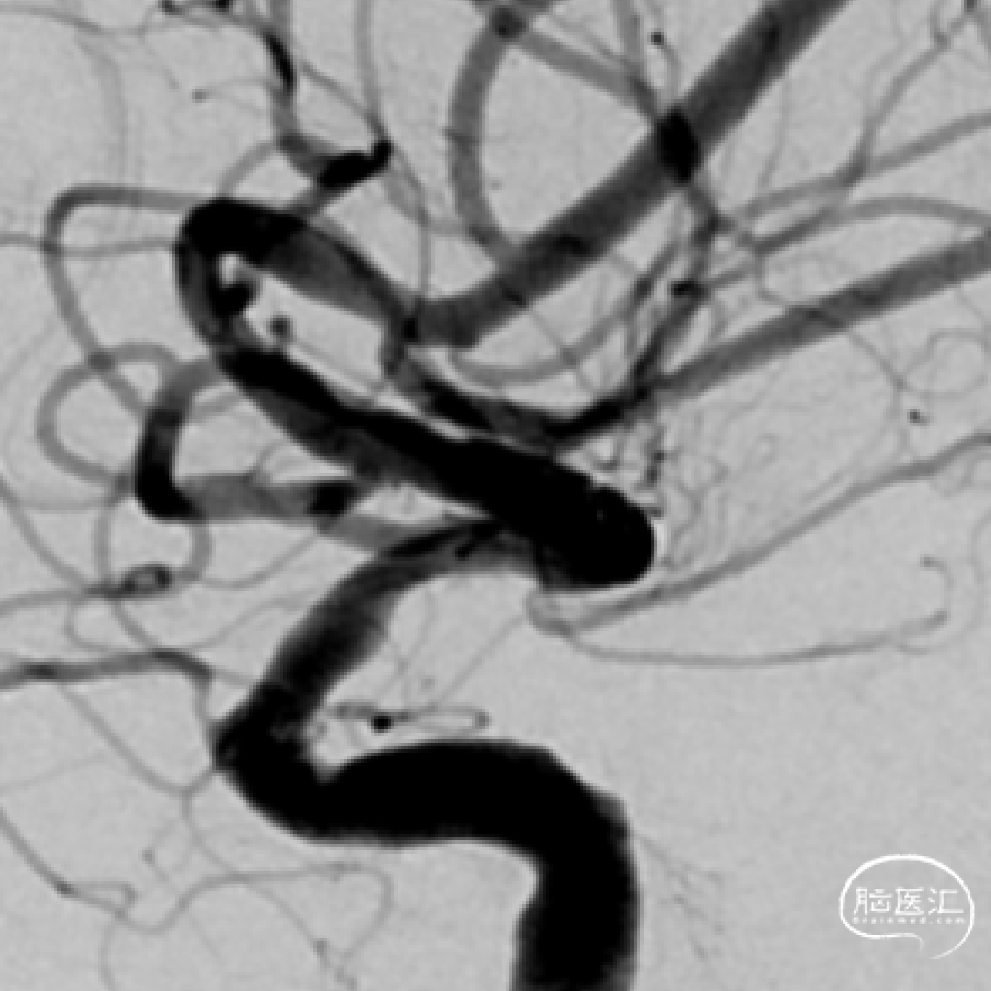

➢DSA(2023.11.10)

颅内球囊 2.25*15mm扩张,扩张至10个atm。

狭窄改善。

植入Atlas支架,动脉瘤不显示,狭窄改善。